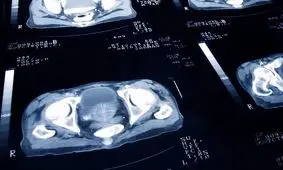

درمان سرطان پروستات پیش از اینکه شیوع پیدا کند راحتتر است. با این حال، در برخی موارد روند رشد سرطان به قدری کند است…

دبیر جامعه اورولوژی ایران گفت: سرطان پروستات دومین سرطان شایع در میان مردان ایرانی است که در صورت تشخیص و درمان به…